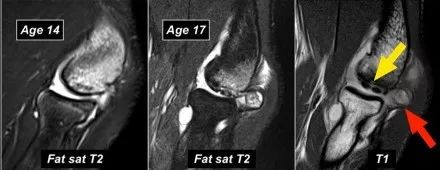

下面这些图像是一名年轻的棒球运动员,在14岁时出现肘部疼痛。T2W-fatsat图像显示骨髓水肿,并且可能存在软骨下骨折。

然而他要继续投掷,因为他三年后在17岁时才来就诊。T1W图像显示碎片(黄色箭头),游离体(红色箭头)。T2W图像表明片段不稳定,因为片段和肱骨之间存在高信号。

在关节镜检查中,肱骨小头骨软骨有凹陷和不规则。

取出的游离体。